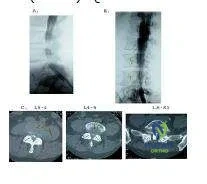

Question 13:

A 70-year-old man complains of severe, burning pain in both calves after he ambulates approximately one block. He denies significant back pain. He has long-standing, insulin-dependent diabetes mellitus and a history of coronary artery disease. The patient has smoked two packs of cigarettes each day for more than 30 years. A magnetic resonance image (MRI) of the patient is obtained (Slide). What does the MRI show:

Options:

- C ritically severe stenosis at L3-L4 and L4-L5

- Moderate lumbar spinal stenosis at L3-L4 and L4-L5

- Herniated lumbar disk

- Moderate lumbar stenosis at L3-L4, L4-L5, and L5-S1

- Lumbar metastatic disease

Correct Answer: Moderate lumbar spinal stenosis at L3-L4 and L4-L5

Explanation:

The MRI shows moderately severe lumbar stenosis at L3-L4 and L4-L5. While the degree or severity of stenosis remains subjective, terming this stenosis critical is an exaggeration. The section of the axial images at L5-S1 is not in plane with the disk, hence there appears to be lateral recess stenosis at this level also. The sagittal images, however, do not confirm this diagnosis. There is no evident lumbar disk herniation, and there are no findings indicative of lumbar metastatic disease.